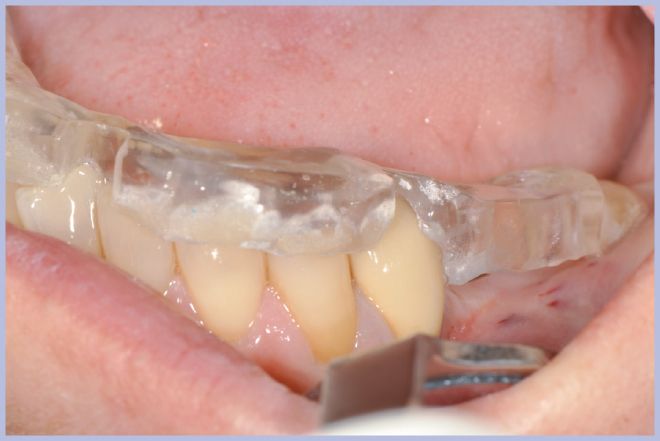

Per riabilitare la masticazione del terzo quadrante, con osso gravemente atrofico, si procede allo studio del caso con esame radiologico 3D e posizionamento virtuale di impianti Exacone® Leone. La prima valutazione è stata eseguita con il software dell’apparecchio radiografico Cone Beam presente in studio. Dopo aver verificato che la quantità di osso residuo fosse sufficiente all’inserimento di due impianti, seppur di dimensioni ridotte, in sede 3.5 e 3.6 senza l’ausilio di tecniche di rigenerazione ossea (Figg. 1-3), si richiede al laboratorio di confezionare una mascherina radiologica con ceratura diagnostica radiopaca e repere standardizzato a livello incisale come da protocollo Leone (Figg. 4, 5). Si verifica quindi clinicamente l’assenza di mobilità della mascherina dopo il posizionamento nel cavo orale del paziente (Figg. 6, 7). Si effettua una CBCT con la mascherina in posizione e l’esame viene inviato in formato DICOM all’azienda Leone assieme al modello master della paziente. L’azienda provvede quindi ad inviare agli Autori il software 3Diagnosys (software di progettazione) in licenza monopaziente con caricati i file DICOM ricevuti; il software viene quindi utilizzato per la progettazione definitiva del caso (Figg. 8-12).

- Figg. 4, 5 – Realizzazione della mascherina radiologica

- Fig. 5